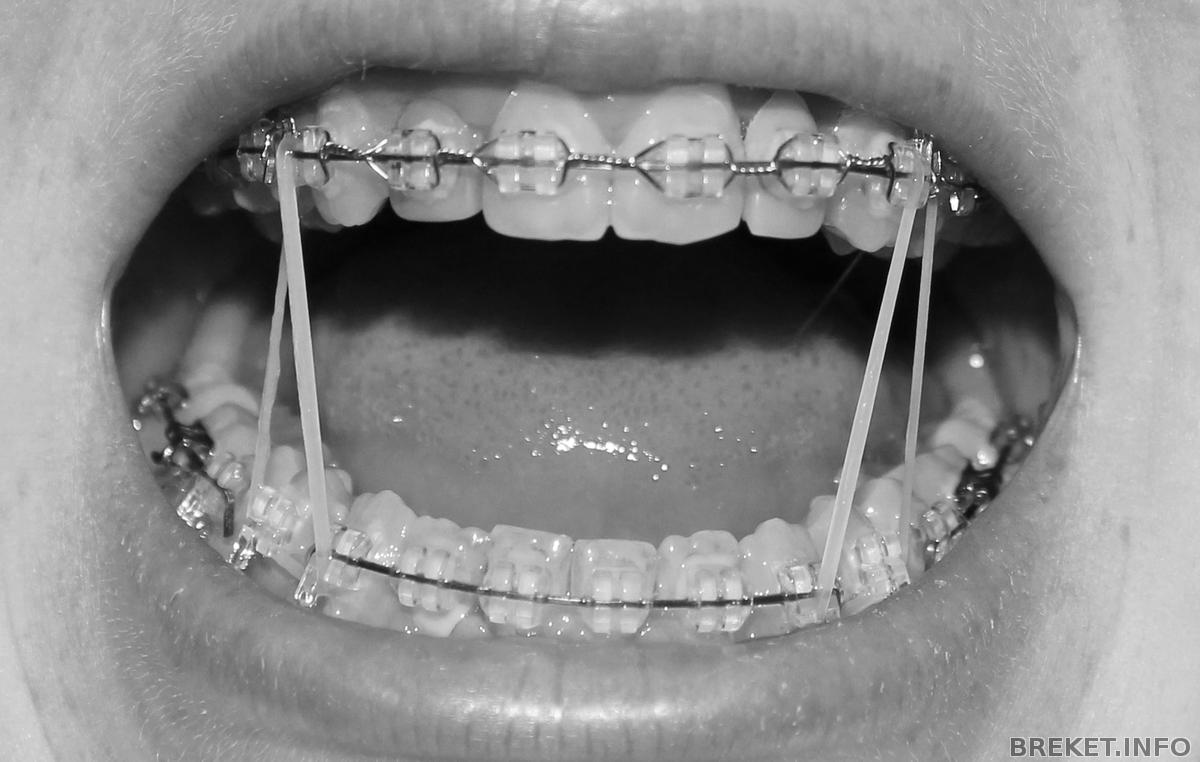

Дела обстоят так,за месяц до снятия, клык справа упирается, и упирается очень сильно, слева щель между челюстями давно закрыта. А тут до сих пор не до конца. Уже год хожу с тягами.

img_8267.jpg

Меся до снятия 2.

Так сейчас(вижу что низ с одной стороны выше, ибо гребаный клык сверху умудряется тянуть зубы к себе,а не опускаться сам,и с этим ничего не придумать:(); Читать далее »